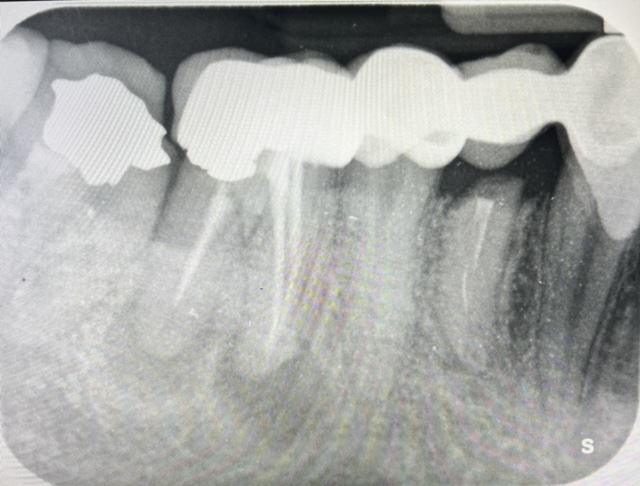

CASI IMPLANTOLOGIA DENTALE

CASO 1